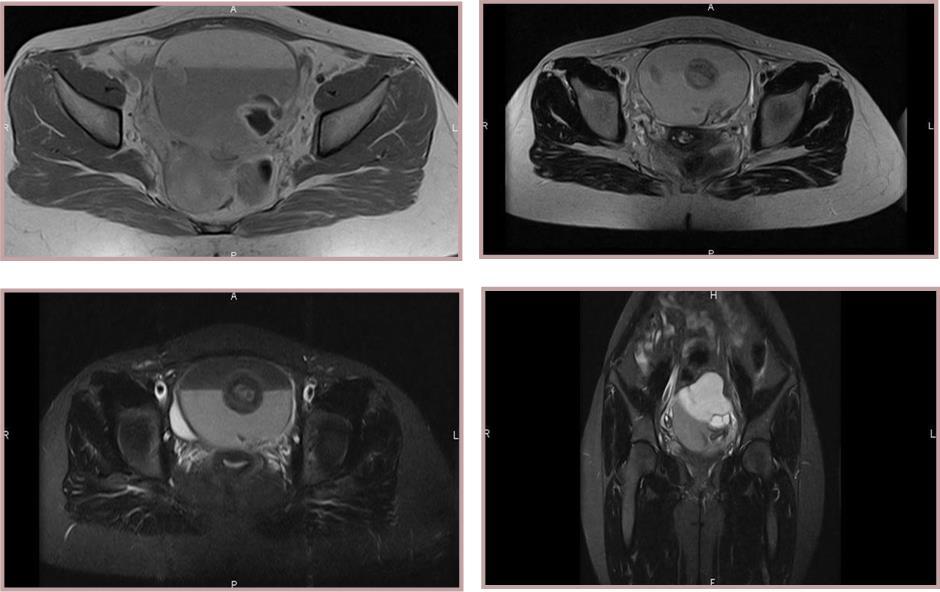

A transabdominal or transvaginal ultrasound reveals a large hyperechoic mass with posterior shadow-cone because of the sebaceous and hair materials or a hypoechoic cyst if it contains only sebaceous material liquid. The bones and teeth appear hyperechoic 8. MCT are sometimes difficult to distinguish on ultrasound from hemorrhagic cysts, mucinous cystic neoplasm and endometriomas 9. In these cases, the magnetic resonance imaging (MRI) plays an important role in diagnosis. Cystic teratoma appears as a large pelvic monocular cyst with a solid nodule named Rokitansky protuberance attached to a thin wall and protrudes in the cyst lumen. Figure 2 Standard T1 weighted images with fat saturated T1 weighted images establish the diagnosis when the fat removed and the fluid-fat levels is also seen. The sebaceous component of cystic teratoma is hyper-intense on T1-weighted images Figure 4. Findings of calcifications are variable and difficult to detect. Figure 3 However, 7% of MCT don't contain any fat or calcifications 10. IV contrast gives a small nodule and wall cyst enhancement. The relationship between the teratoma and other anatomic pelvic structures can be well evaluated 11.

Figure 1(a,b,c,d ).Two lesions within cystic component measuring 6 x 7 x 8 cm. MRI reveals a large and well-defined encapsulated tumour. Two solid components with an intermediate signal in T2 and T1 with a moderate contrast enhancement on T1 weighted.